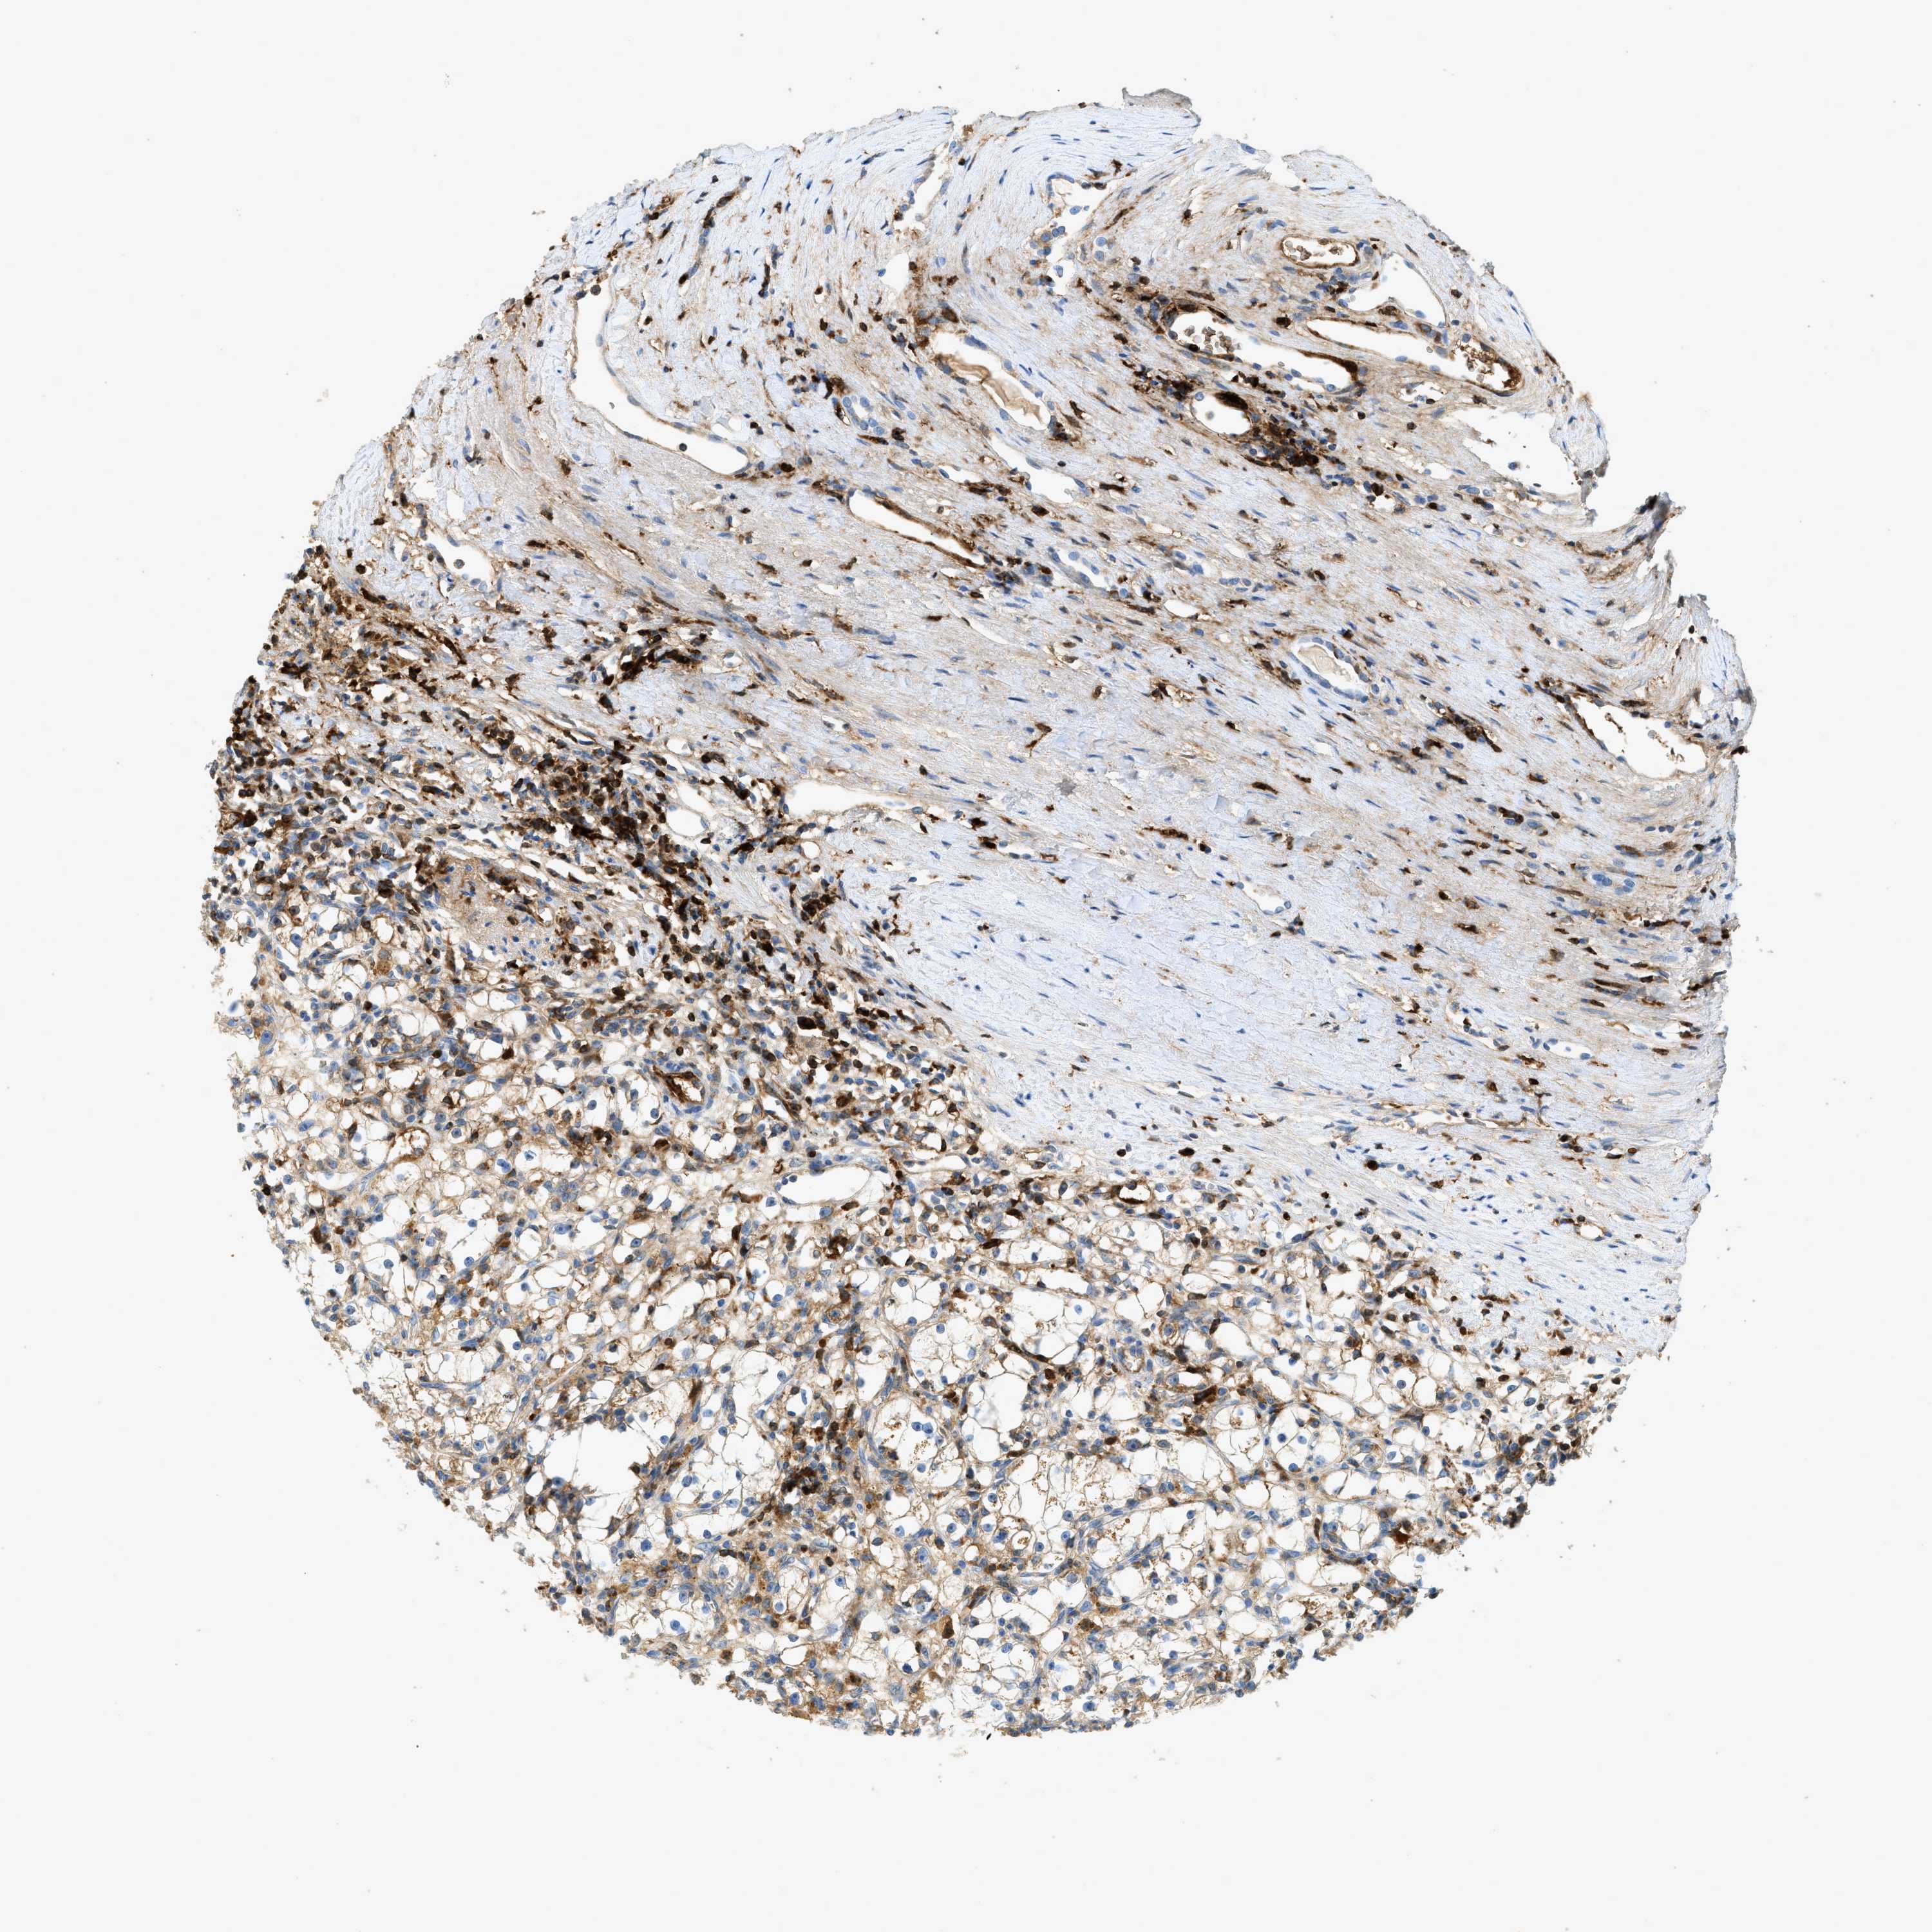

CANCER RENAL CANCER Show tissue menu

KICH TCGA KIRC TCGA KIRC VALIDATION KIRP TCGA PROTEIN RCC CPTAC PROTEIN EXPRESSION